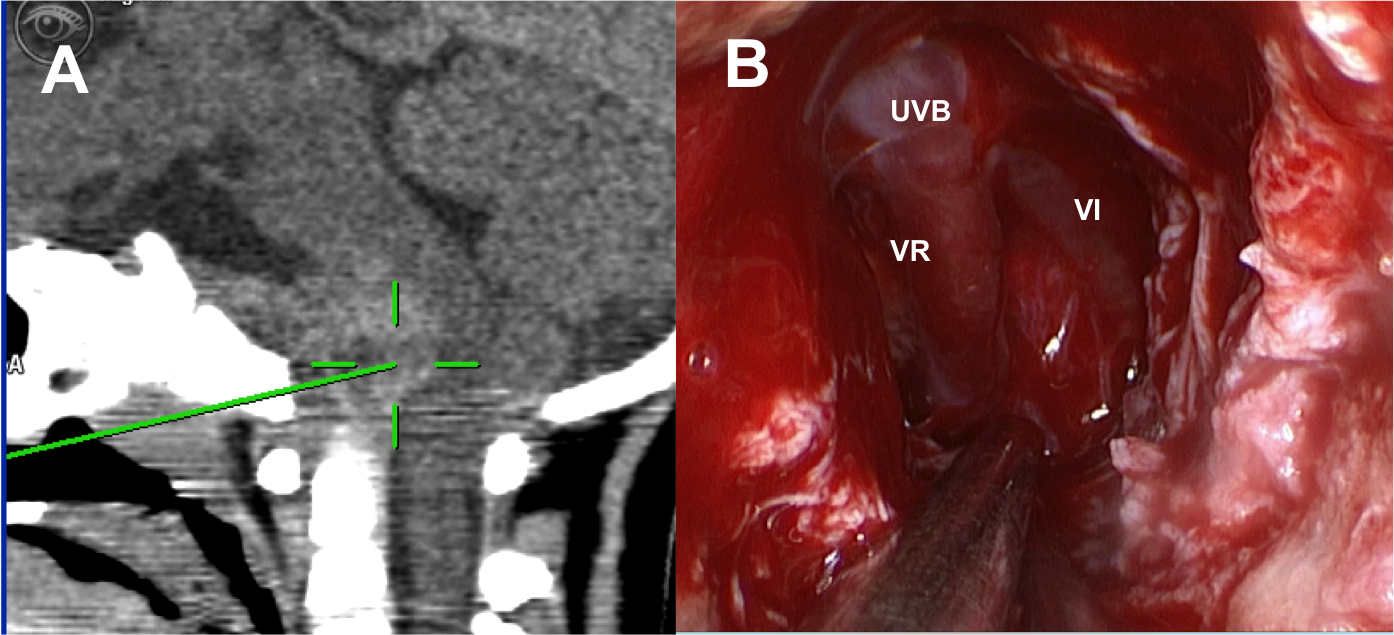

Introducción: La cirugía endoscópica endonasal se ha convertido en una herramienta fundamental para el manejo de patologías que comprometen la base de cráneo. En casos bien seleccionados, estas técnicas permiten resecciones quirúrgicas con una menor morbilidad sin comprometer los principios oncológicos de resección. Con el desarrollo de instrumental especializado, nuevas tecnologías y la experiencia de los cirujanos, la cirugía endoscópica endonasal se usa cada vez más en cirugía de base de cráneo en niños.

Diseño: Estudio observacional descriptivo de tipo serie de casos. Metodología: se describe la experiencia con pacientes pediátricos llevados a cirugía endoscópica endonasal para manejo de tumores de base de cráneo en el Instituto Nacional de Cancerología entre julio de 2014 y diciembre de 2016.

Resultados: Fueron intervenidos 8 pacientes entre los 2 y 14 años, con una edad promedio de nueve años y un seguimiento promedio de 16 meses. En el 75% se hizo una resección total del tumor. Un paciente requirió una reintervención y un paciente fue sometido a radiocirugía post-operatoria. 1 paciente falleció a pesar de múltiples intervenciones, quimioterapia y radioterapia.

Conclusión: La cirugía endoscópica endonasal para tumores de base de cráneo puede ser utilizada de forma segura en los pacientes pediátricos, es una técnica que en casos bien seleccionados pueden ofrecer excelentes resultados disminuyendo la morbilidad y complicaciones de las técnicas abiertas.